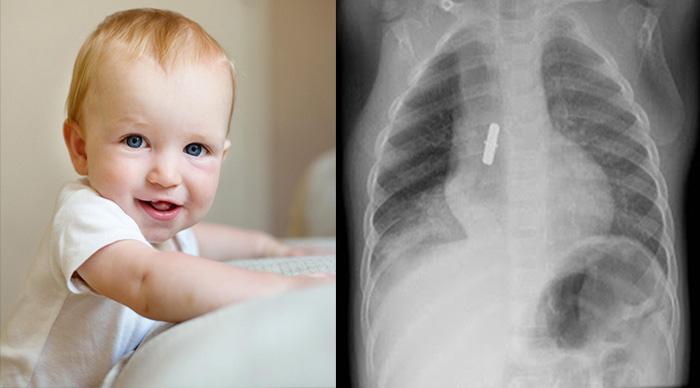

ΥΓΕΙΑ 26.10.24 Διάμεση πνευμονίτιδα : Τά συμπτώματα της ασθένειας που πέθαναν τα βρέφη από την Αμαλιάδα